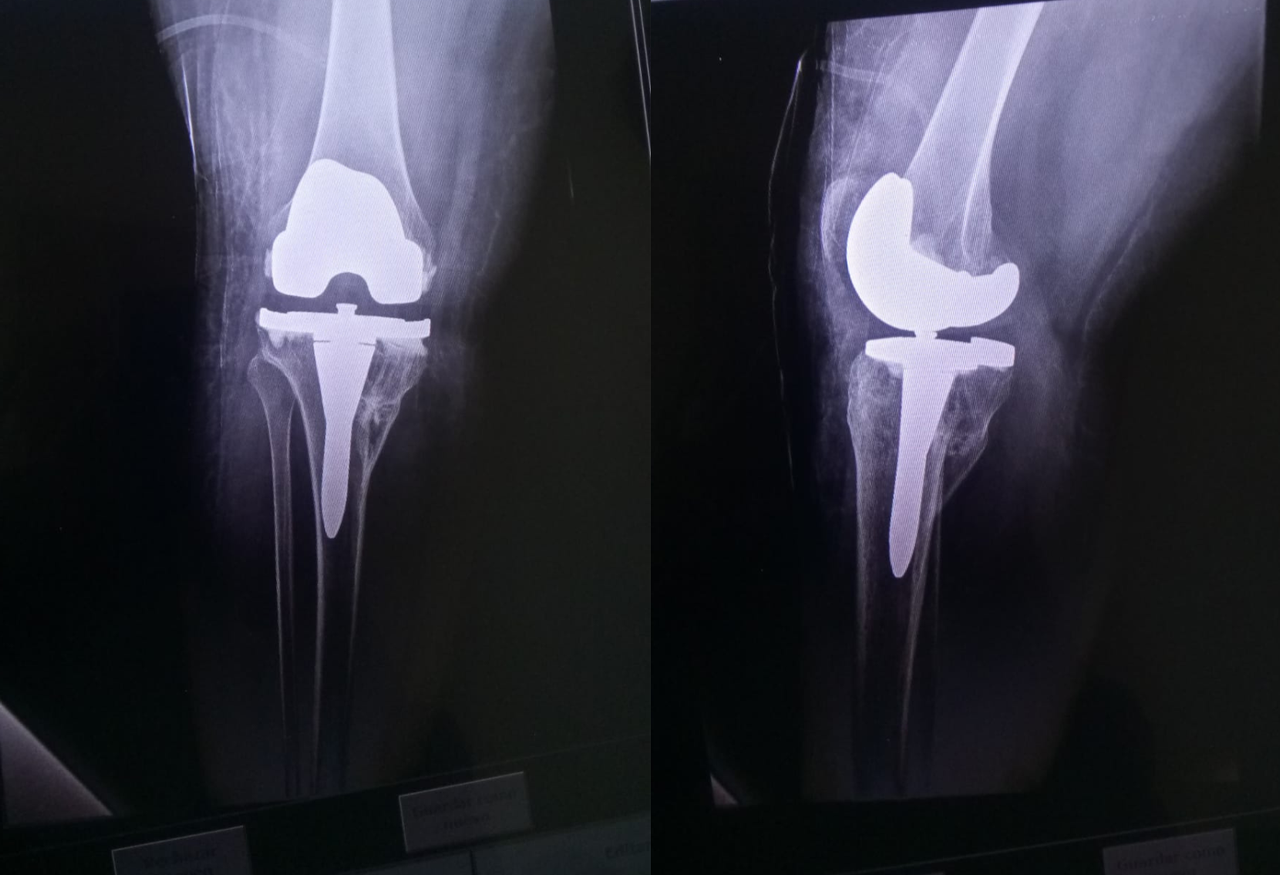

Protesis_de_rodilla

Prótesis de Rodilla.

Cirugía de reemplazo de la articulación de la rodilla por una prótesis artificial en pacientes con desgaste severo o daño articular, ayudando a recuperar la función y disminuir el dolor.